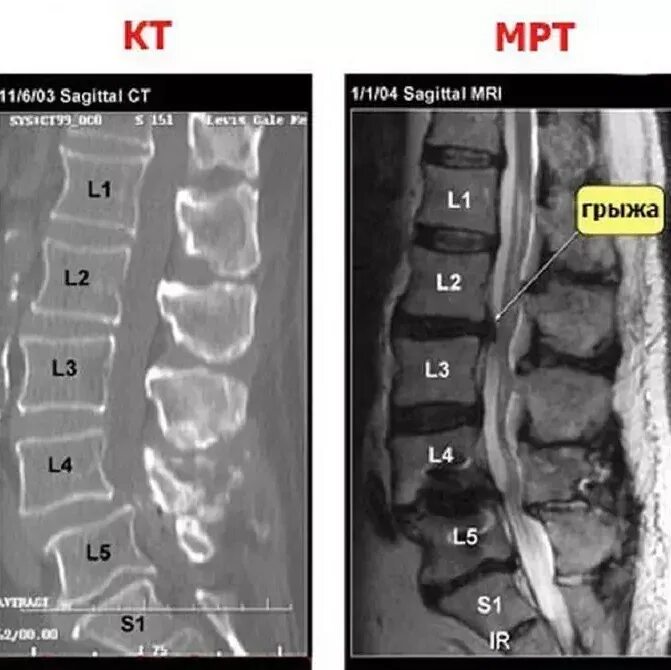

Мрт или кт позвоночника при болях